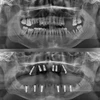

التهاب ما حول الغرسات السنية

نقص الأسنان

تسوس الأسنان

أكياس الفك

التهاب مخاطية ما حول الغرسة

أمراض الأسنان واللثة

اعوجاج الأسنان